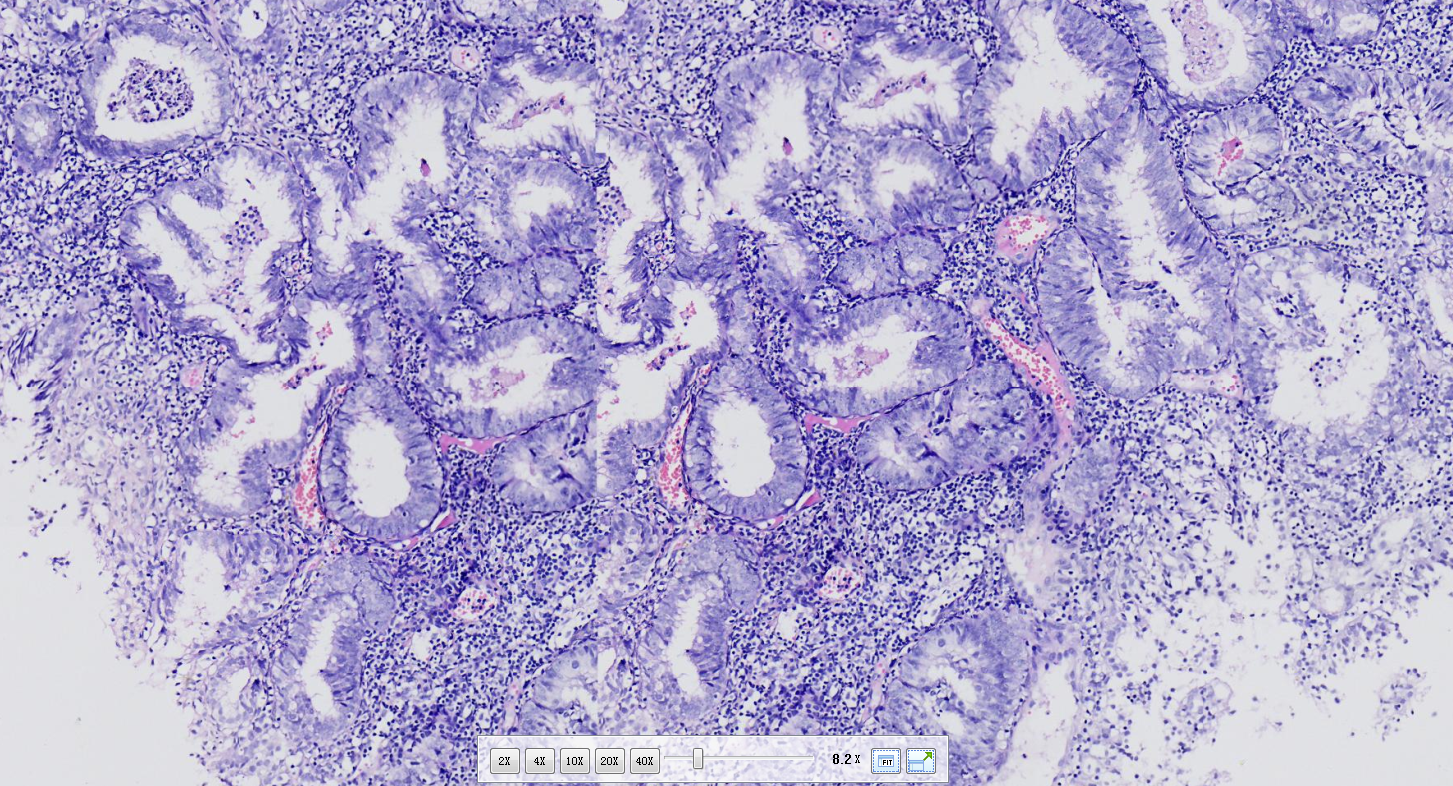

性别

女

年龄

62岁

不规则出血半年

子宫内膜(刮宫)

灰红软组织一堆,体积0.5*0.4*0.3cm。

临床情况:月经史?之前有无诊刮及诊断?有无用药?内膜呈高分泌相改变,部分腺体呈非典型增生改变。

非典型性子宫内膜增生。